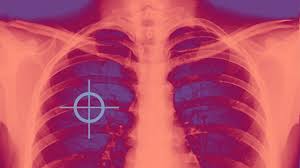

It can also be seen on computed tomography scans or chest radiographs. What is the vector of malaria? Symptoms can range from mild to serious and may include a cough with or without mucus (a slimy substance), fever, chills, and trouble breathing. Lung cancer screening refers to testing a healthy individual at high risk for developing lung cancer who has no symptoms of lung cancer to find lung cancer at a stage that it can be better treated. So, you might wonder what are the symptoms of lung cancer.

Symptoms of lung cancer develop as the condition progresses and there are usually no signs or symptoms in the early stages. Symptoms of lung cancer can include a persistent cough, shortness of breath, coughing up blood, arm or chest pain, and unexplained weight loss. The diagnosis of lung cancer is confirmed through biopsy by bronchoscopy. How serious your pneumonia is depends on your age, your overall health, and what is causing your infection. Once lung cancer has spread beyond the lungs, it's generally not curable.